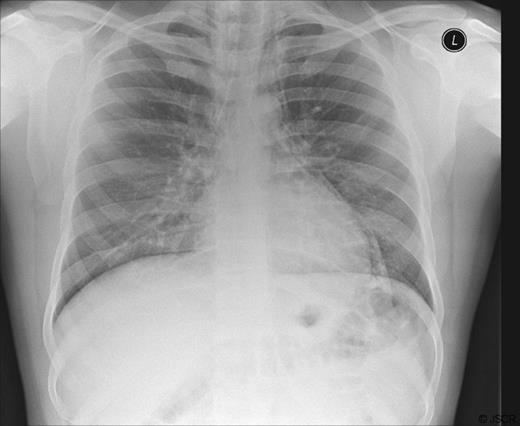

His blood tests showed a CRP 36, with all other hematological and biochemical parameters within normal levels. An electrocardiogram and serum troponin were unremarkable. A chest X-ray (Fig. 1) was performed to exclude pneumothorax but surprisingly revealed pneumomediastinum. He was admitted and transferred to the care of the surgical team with a diagnosis of suspected bronchial or oesophageal perforation. Computer Tomography (CT) Thorax imaging (Fig. 2) confirmed the presence of a pneumomediastinum extending from the lower neck at the level of C6 to the diaphragmatic hiatus. There were no visible mediastinal collections and no evidence of pulmonary /airway disease with intact pulmonary vessels. An oesophageal perforation was suspected but not shown on a water-soluble contrast swallow.